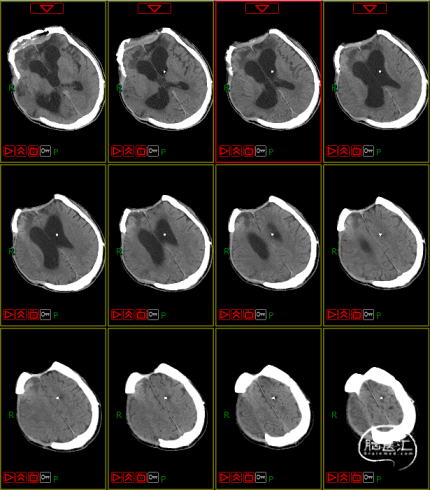

病史及症状描述:主诉:重型颅脑外伤术后意识障碍50天(7月30日入院);现病史:患者2023年6月11日因高处坠落伤在外地行开颅手术等治疗,病情平稳后带气管套管转回湘潭市中心医院(后续简称“我院”)治疗。

入院查体:GCS=E2VTM2=4T分,右侧瞳孔直径约4mm,对光反射迟钝,左侧瞳孔约3mm,对光放射灵敏,四肢关节被动屈伸活动无受限,四肢肌张力偏高,肌力查体无法配合,病理征未引出。

入院诊断:1. 右侧额颞部硬膜下血肿清除术后;2. 颅骨后天性缺损;3. 脑内多发软化灶形成;4. 脑积水;5. 左额骨凹陷性骨折;6. 颅底骨折;7. 左股骨干骨折内固定术后;8. 坠积性肺炎、胸腔积液;9. 气管切开术后;10. 右眼挫伤;11. 下肢肌间静脉血栓;12. 低蛋白血症。

4. 动态复查头部CT

8月21日复查CT:硬膜下积液增加,脑室扩张明显,间质性水肿加重;对患者治疗方案进行调整,转神经外科治疗。